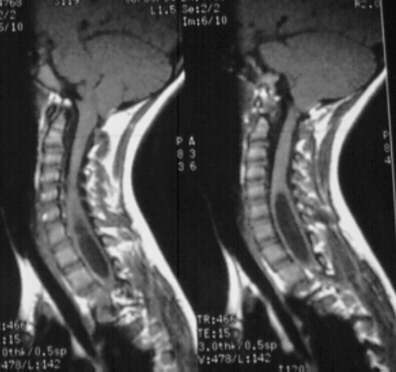

MRI, especially sagittal images, are best for detecting Chiari malformations and syringomyelia

- Chiari I (image at right)

- (in 40%) syringobulbia, hydromyelia, or syringomyelia

- also can have hydrocephalus